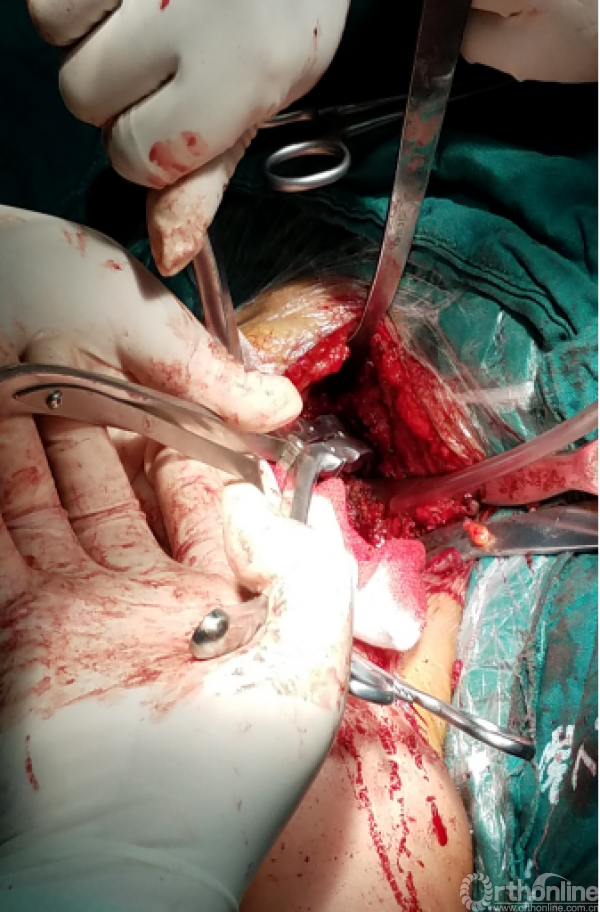

安尔碘溶液反复冲洗1000毫升,浸泡!!!

1.抗生素骨水泥占位器植入

2.不锈钢克氏针+抗生素骨水泥

3.柄部没有骨水泥,利于引流,头部较原有假体头部偏大,减少挛缩,占位关节腔,颈干角及后倾维持

4.用肌腱缝线固定减少排斥

5.后内侧结构尽量不去干扰,防止出现神经血管损伤。